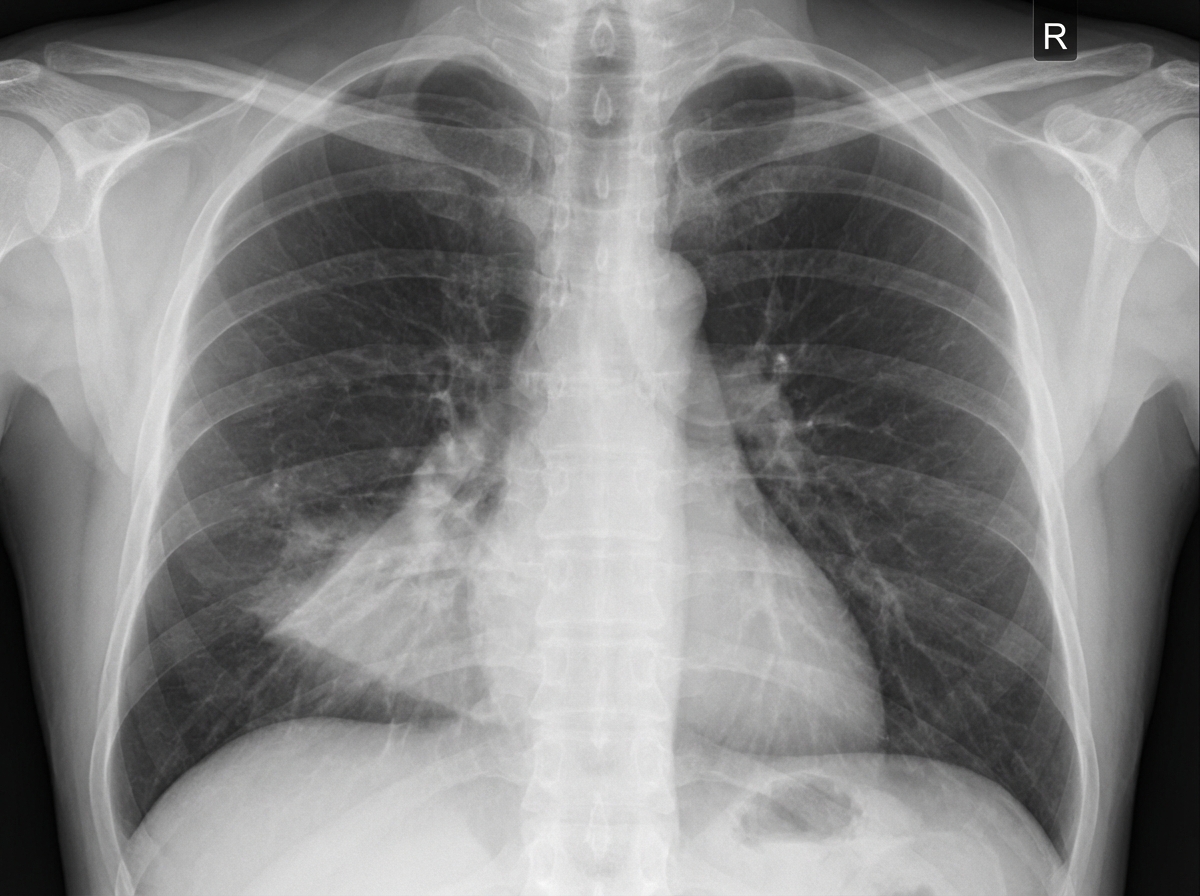

A previously healthy 46-year-old woman comes to the physician with a one-week history of productive cough and fatigue. Two weeks ago, she had fever, nasal congestion, rhinorrhea, and myalgias that resolved with supportive care. She has not traveled out of the United States. Pulmonary examination shows dullness to percussion and increased fremitus at the right middle lobe. An x-ray of the chest is shown. A sputum sample is most likely to show which of the following findings?